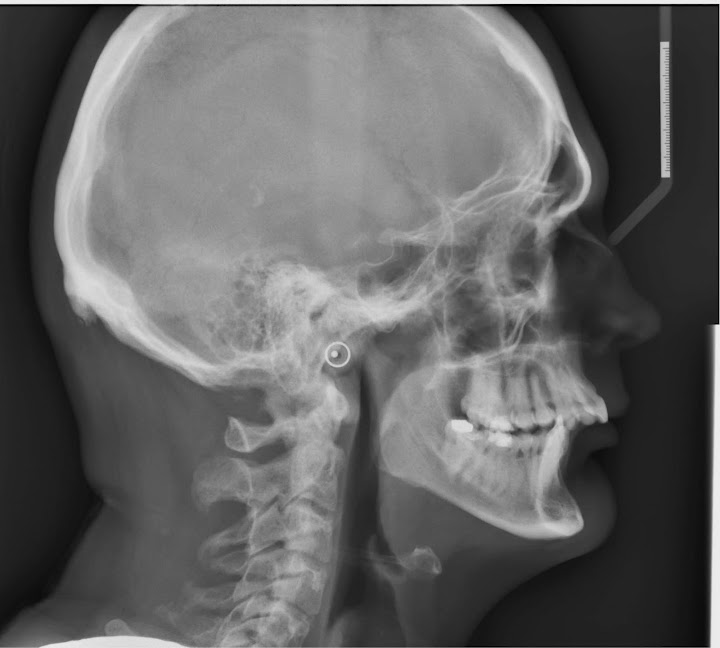

Temporomandibular Joint Disorder (TMJ) and Dislocated Jaw Patient's

From patientslounge.com

Temporomandibular Joint Disorder (TMJ) and Dislocated Jaw Patient's Jawline X Ray An easy way to check how wide your mouth can open is to try to put 3 fingers vertically between your lower and upper front teeth. Jaw cancer can affect either the lower jaw, called the mandible, or the upper jaw, the maxilla. Jaw cancer is a rare type of head and neck cancer and one of many types of. Jawline X Ray.